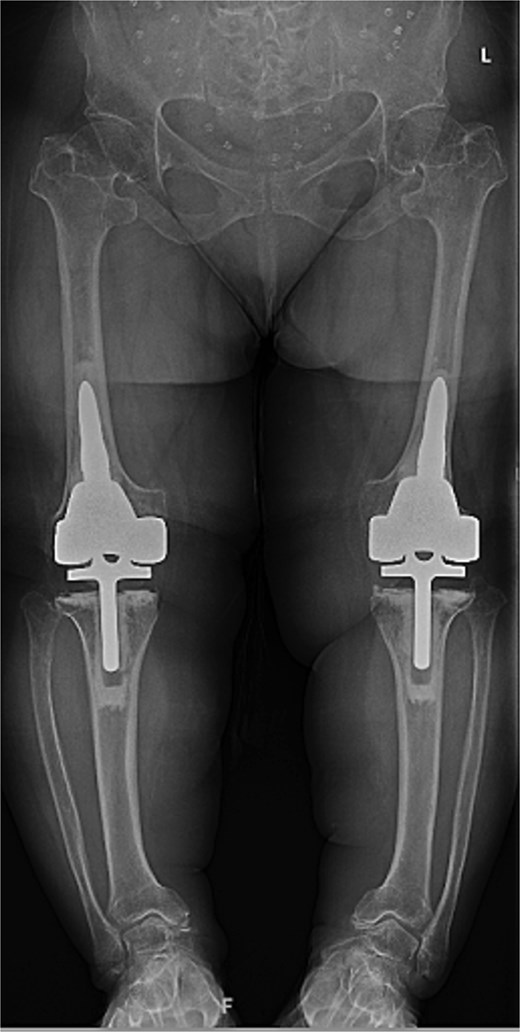

At the 2-year follow-up, the patient reported no significant pain, demonstrated a normal gait, and had active bilateral knee range of motion from 0° to 125°. There was no joint line tenderness or instability. Surveillance radiographs confirmed well-aligned and stable components with no evidence of implant failure or periprosthetic lucency (Fig. 3). At the five-year follow-up, the patient remained very satisfied with her knees and denied knee pain. On exam, her gait was slightly antalgic, but active bilateral knee range of motion remained preserved at 0° to 120°, and both knees remained stable throughout range of motion and nontender to palpation. Radiographs continued to show stable prosthetic components without evidence of implant failure or periprosthetic lucency (Fig. 4).

Two-year postoperative AP radiographs demonstrating stable, well-fixed components with appropriate alignment and no evidence of implant loosening or periprosthetic lucency.

Five-year postoperative AP radiographs showing continued stability of bilateral rotating-hinge implants with maintained alignment and no radiographic evidence of implant failure.